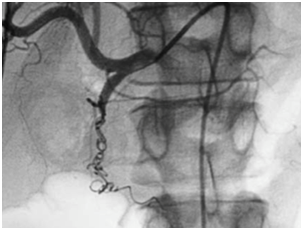

Embolization of upper gastrointestinal bleeding in oncological patients is commonly performed with a combination of agents: gelatin sponge (Gelfoan), coils, microcoils, and particles. These embolic agents function similarly to surgical ligation by decreasing perfusion pressure to the bleeding site; the reduction of blood flow promotes clot formation. Due to the dual blood supply of the stomach and duodenum, the risk of bowel ischemia is minimal when embolization is performed with coils and absorbable gelatin sponges. The catheter or microcatheter should be inserted into the selected artery in order to avoid deployment of embolic materials in undesired areas. This technique prevents ischemia or infarction, common complications of the procedure (Figure 1 & 2).

Figure 2 Common hepatic arteriogram after embolization with coils and gelatin sponge shows occlusion of the gastroduodenal artery.